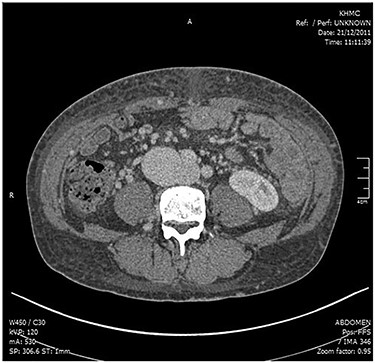

A physical examination showed hepatomegaly, bilateral lower limb pitting edema (more on the right side), a continuous bruit in the lower abdomen, and increased jugular venous pressure. A cardiac echocardiography showed elevated pulmonary artery pressure, normal left ventricle systolic function, and an enlarged right ventricle. A venous duplex showed DVT in the right femoral and popliteal veins. Computed tomography angiography (Fig. 1) with 3D reconstruction revealed an arteriovenous communication between the right iliac artery and the IVC at the level of L4/L5, which was the site of the previous disc surgery, as well as a dilated IVC with a diameter of 7 cm.

CT angiogram showing the connection between the right iliac artery and the IVC.